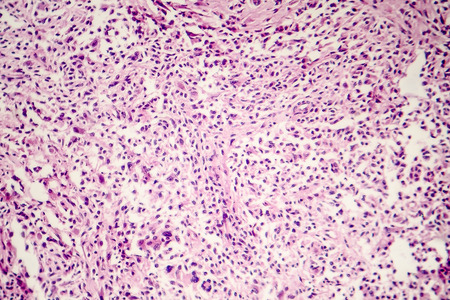

Результат поиска по запросу: "sarcoma"